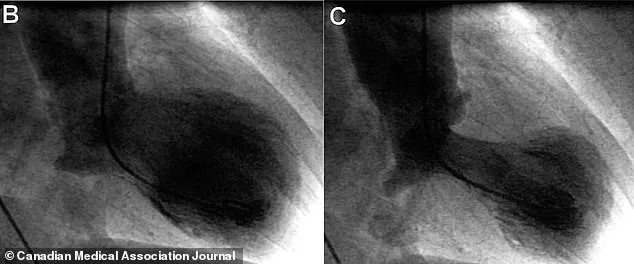

Diagnosis involves a process of elimination. Doctors first rule out a heart attack through tests like echocardiograms, which reveal the characteristic 'takotsubo' shape of the heart—its main pumping chamber balloons at the bottom while the base narrows. Cardiac catheterization, a procedure that injects dye into the coronary arteries, is used to confirm the absence of blockages. Blood tests for troponin, a protein released during heart damage, further support the diagnosis.